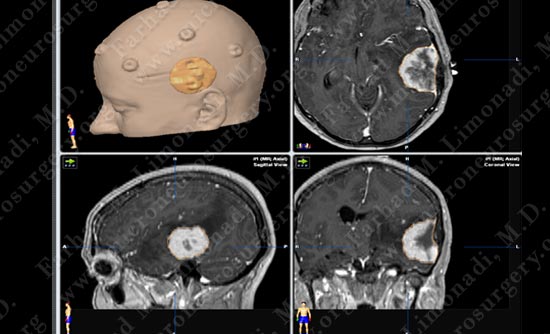

Stereotactic and computer navigation was used to determine the precise location of the tumor (outlined in yellow).